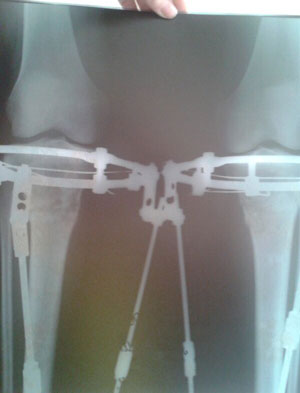

2 месяца с момента операции.

Регенерат растёт хорошо, продолжаем сращение.

Спасибо за совет, Василек! Как на фото ноги мои, ровные со стороны виднее все таки, что- то как -то не пойму какие они получились?!

Привет Adina! Ножки у тебя хорошенькие... Немного иксик есть, но уж лучше так, чем недокрученные. А так они ещё меняться будут с течением времени, так что полностью картинкой ты сможешь насладиться только через несколько месяцев после снятия аппаратов. Как то так...